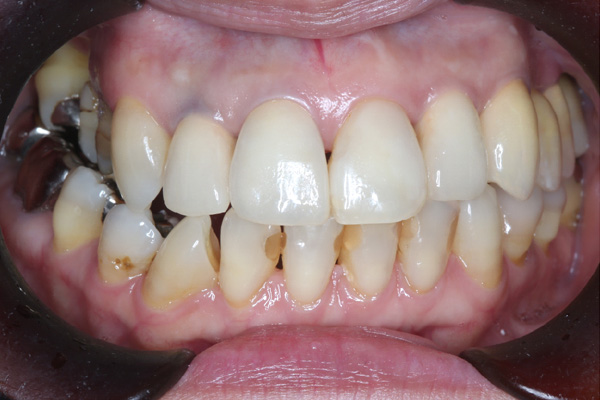

| 年代・性別 | 50代 男性 |

|---|---|

| 主訴 | 前医で前歯を抜かなければならないがインプラントはできないと言われた |

| 治療期間 | 約12ヶ月 |

| 費用 | 600,000円 |

| 治療内容 | インプラント、骨造成、結合組織移植、セラミック修復 |

| 治療に伴うリスク | インプラント周囲炎 セラミックの破折、脱離 |